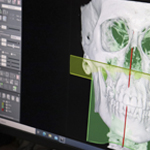

Maxilofacial y Odontología recibieron importante equipamiento

Apoyará procedimientos quirúrgicos

Unidad Neurovascular Innova en el tratamiento de aneurismas

con dispositivo intrasacular

Se concretó la cirugía endoscópica n° 1000 de base de cráneo

y consagra nuevo hito institucional